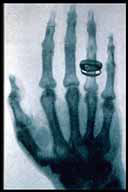

Abbiamo

così appreso che i raggi X furono scoperti dal fisico W.C.

Roentgen nel 1895 per puro caso: mentre "giocava" con un tubo catodico,

un fascio degli elettroni da lui trasmessi colpì una lastra fotografica

posata su uno scaffale del laboratorio.

Roentgen ne capì subito le straordinarie caratteristiche ma non

capì cosa diamine fossero e finì, così, per chiamarli

raggi X.

Si sarebbe poi scopero essere onde elettromagnetiche la cui lunghezza

d'onda è circa 10 volte quella della luce visibile. Essi vengono

prodotti dalla forte decelerazione degli elettroni nelle collisioni con

i nuclei atomici e dalle transizioni degli elettroni nelle orbite più

profonde all'interno degli atomi. Riescono tranquillamente appassare attraverso

le parti "molli" del corpo umano, non attraverso quelle opache: la porima

cosa che si vede in una radiografia, come ben sappiano, è l'apparato

osseo.

Dapprima

i raggi X non furono presi troppo sul serio: divertenti certe diapositive

che Gancarlo ci ha mostrato conseguenti la moda che per quialche rtempo

imperversò di farsi, dal fotografo, le foto dello scheletro...